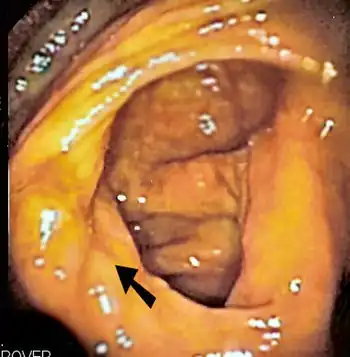

| The ileocecal valve prevents reflux of bacteria from the colon into the small bowel. Resection of the valve can lead to bacterial overgrowth. | |

Finally, abnormal connections between the bacteria-rich colon and the small bowel can increase the bacterial load in the small bowel. Patients with Crohn's disease or other diseases of the ileum may require surgery that removes the ileocecal valve connecting the small and large bowel; this leads to an increased reflux of bacteria into the small bowel. After bariatric surgery for obesity, connections between the stomach and the ileum can be formed, which may increase bacterial load in the small bowel.[26]